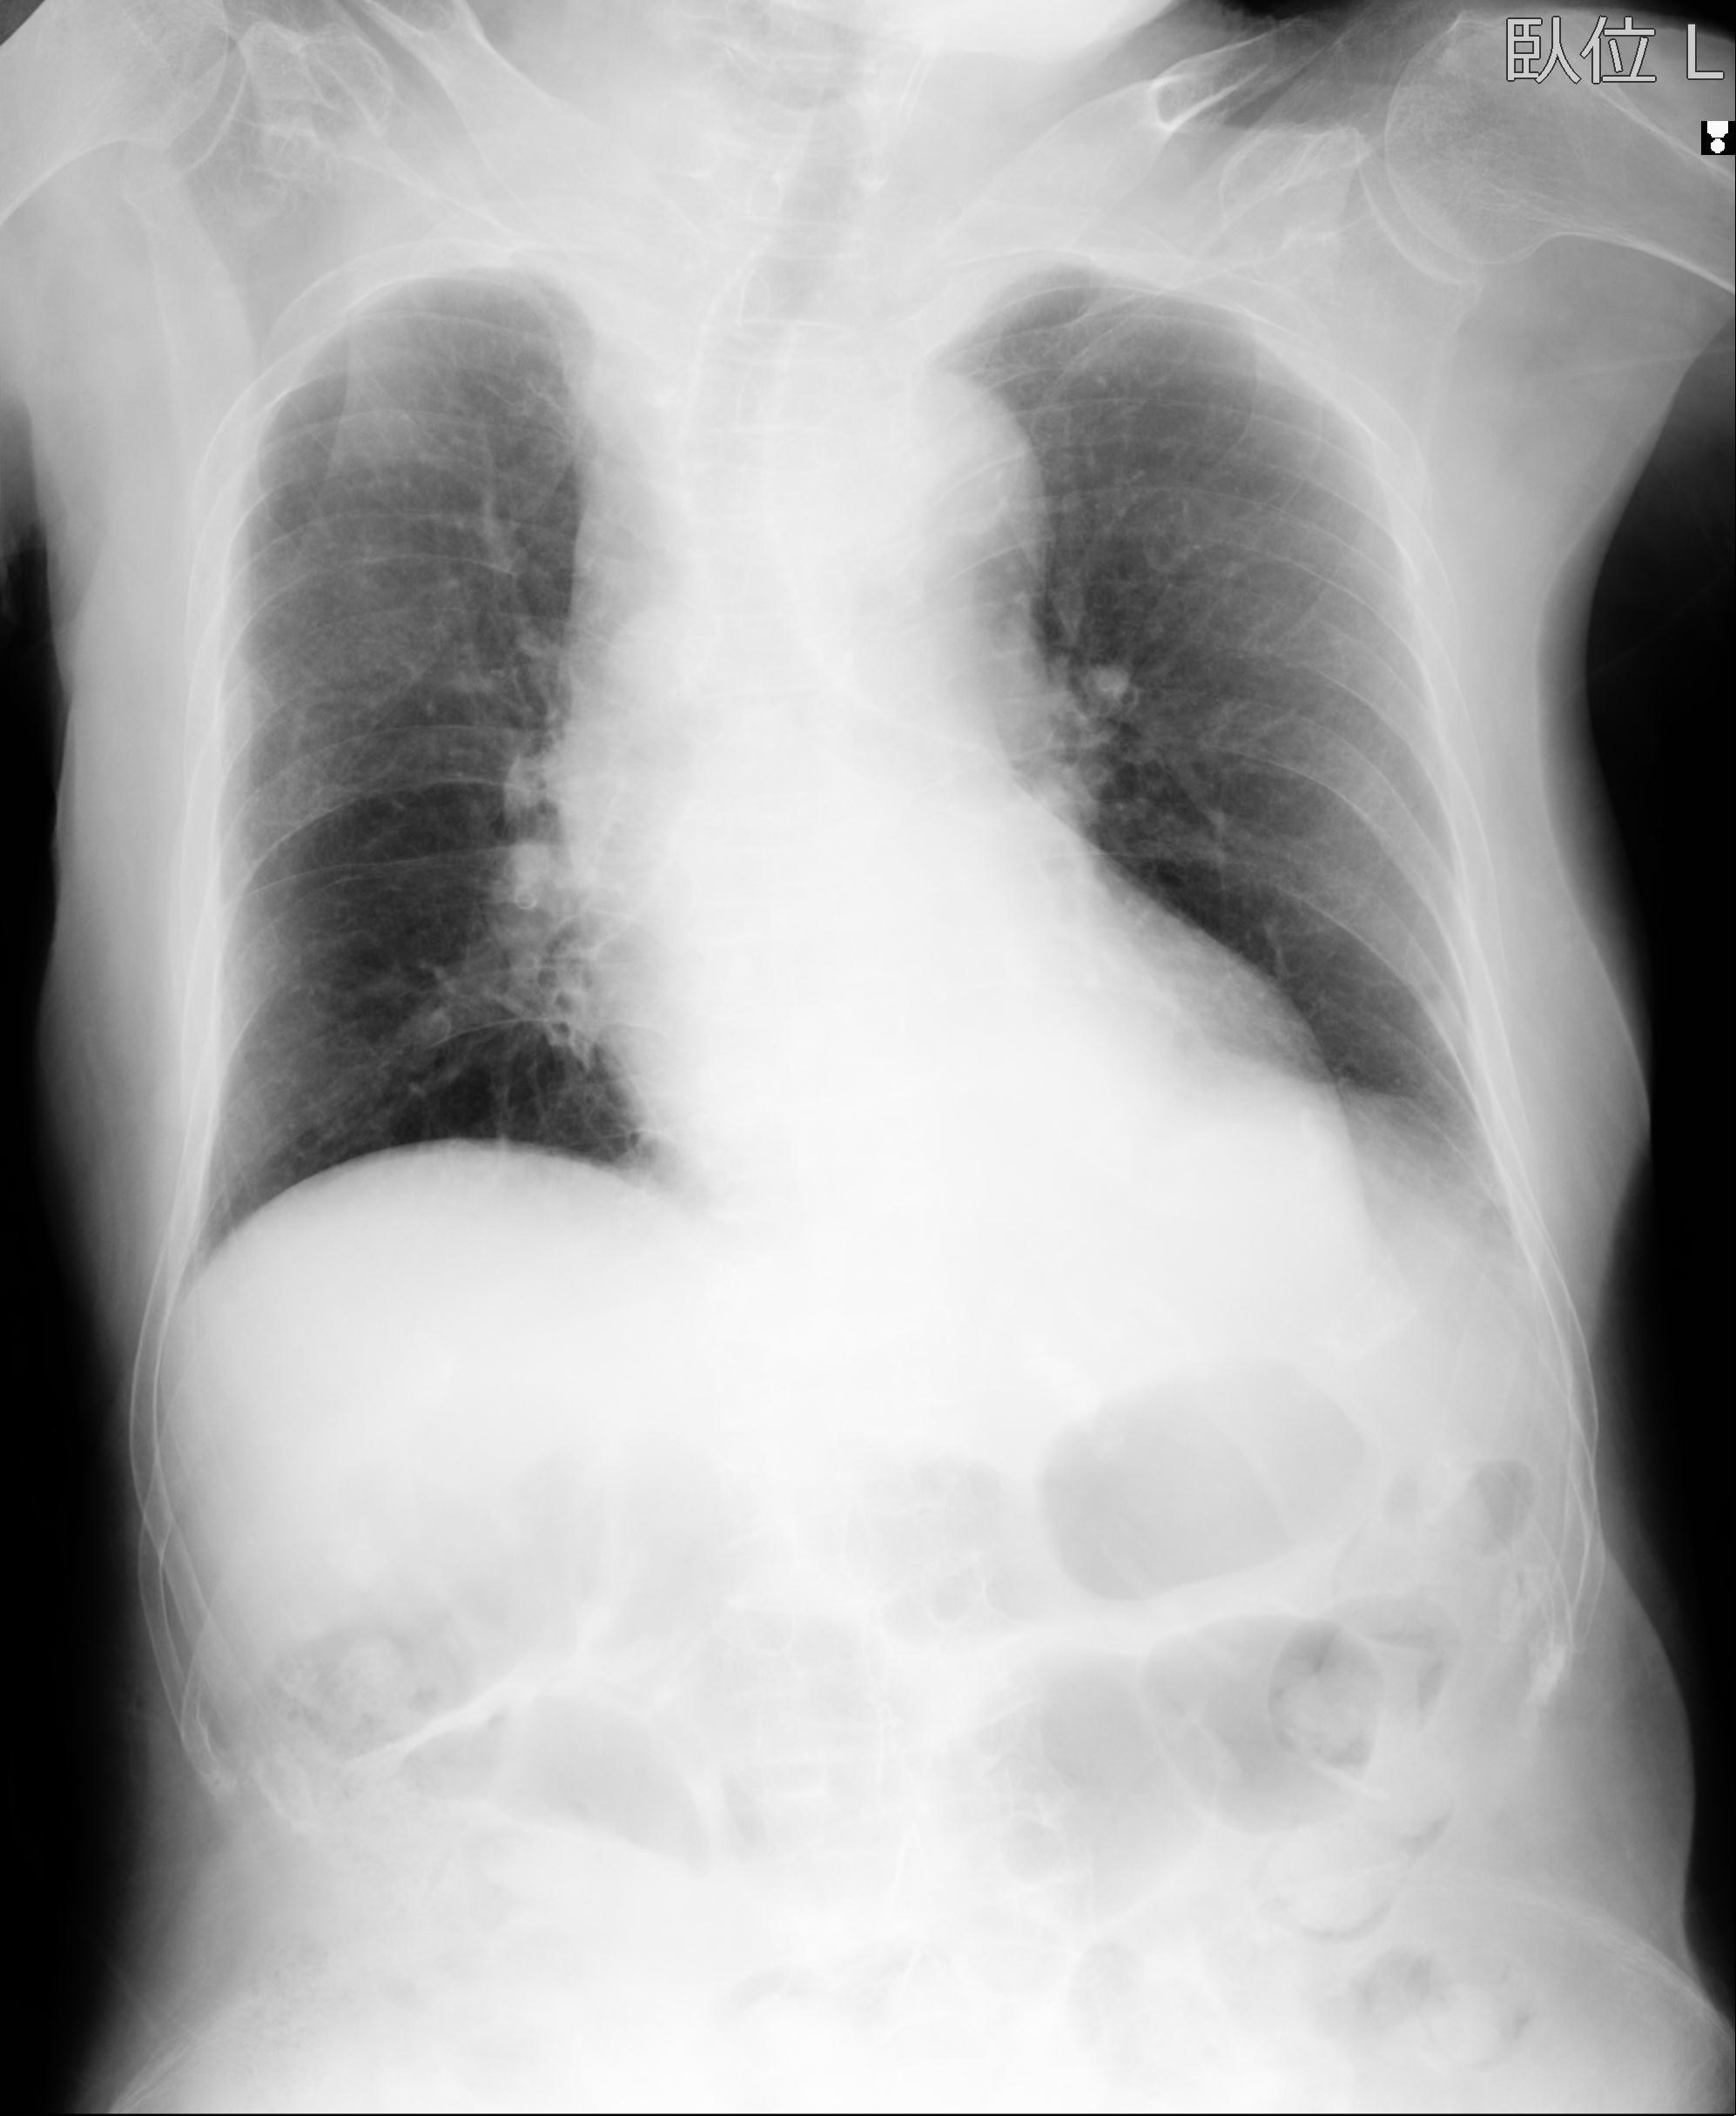

93804 2/9 腰椎 2R 後方固定 67歳女性